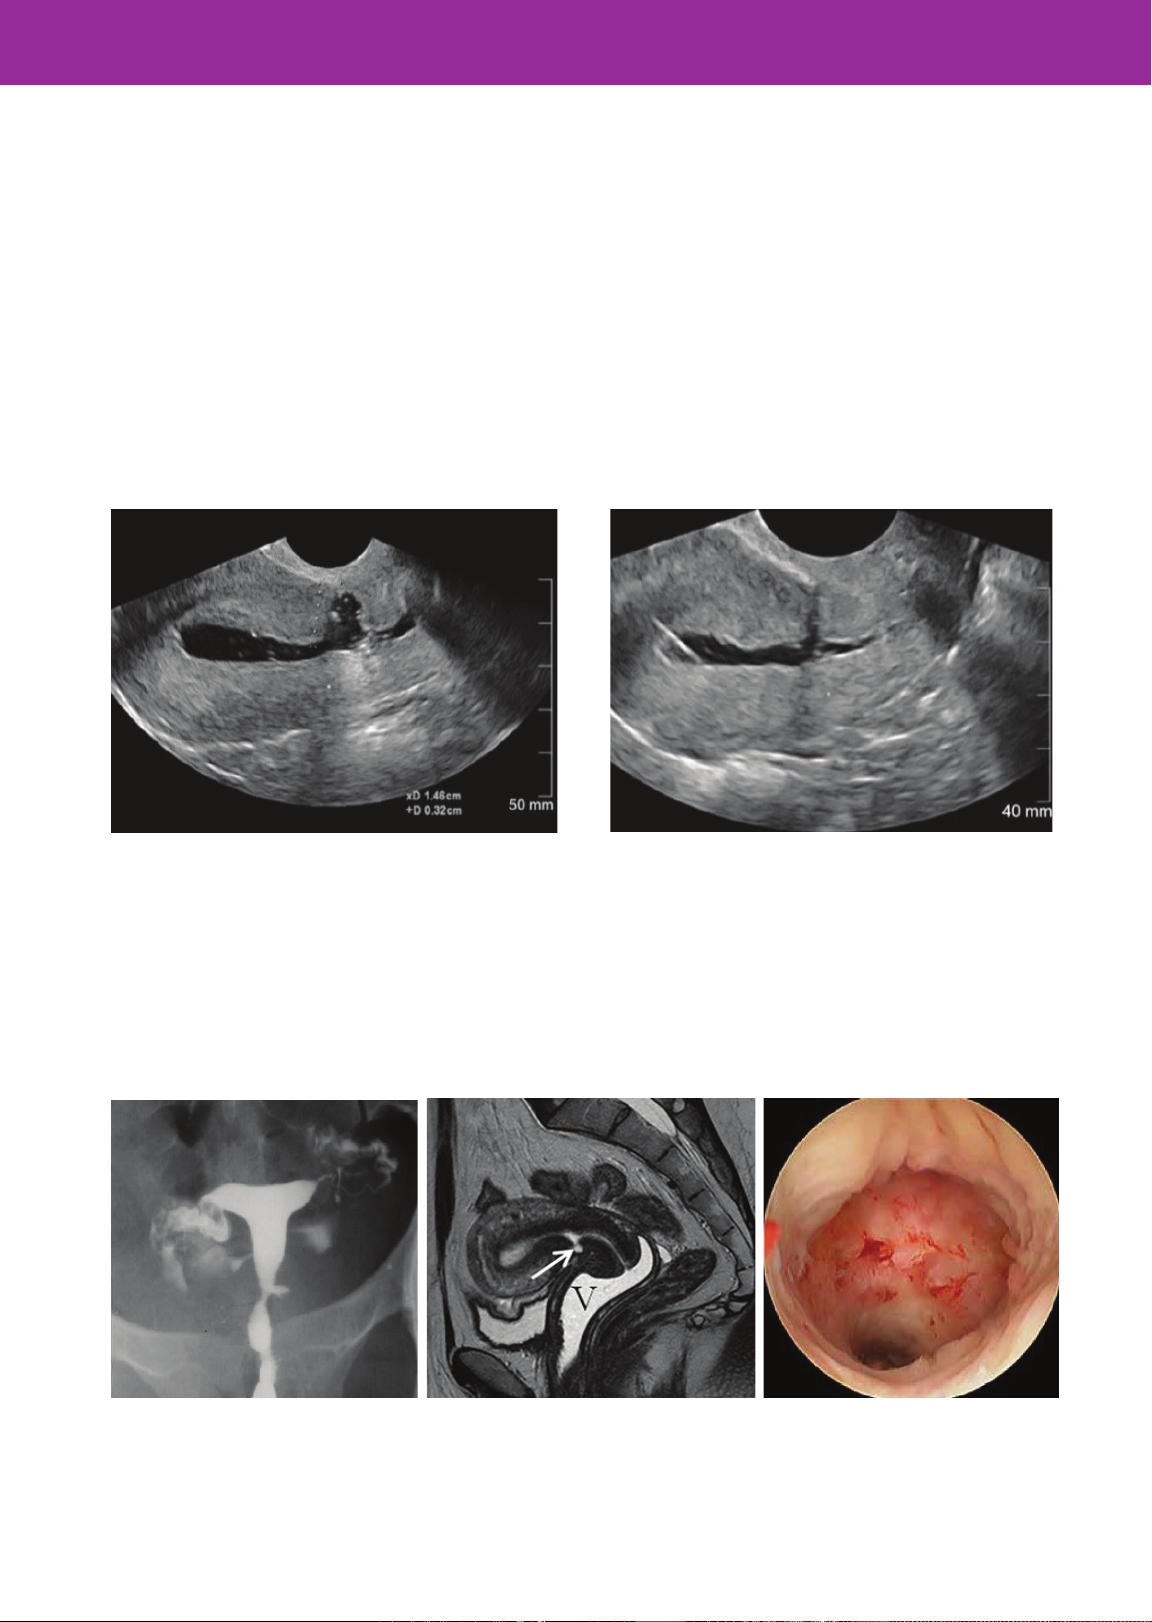

Các phương pháp chẩn đoán hình ảnh khác

nhau bao gồm siêu âm (hình 4,5), chụp

buồng tử cung, nội soi buồng tử cung và

chụp cộng hưởng từ MRI có thể được sử

dụng để xem xét thành trước tử cung và

chẩn đoán lỗ khuyết.18

Hình 4. Lỗ khuyết sẹo MLT to

Hình 5. Lỗ khuyết sẹo MLT nhỏ

Hình 6. Lỗ khuyết sẹo MLT

trên HSG

Hình 7. Lỗ khuyết sẹo MLT qua MRI

Hình 8. Lỗ khuyết sẹo MLT qua

nội soi